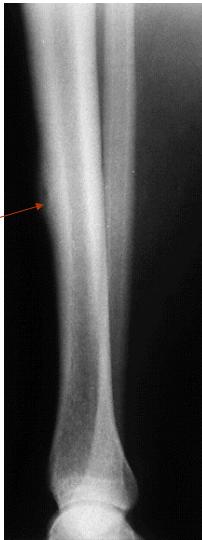

Other Diaphyseal Lesions

Could be malignant, even though no periosteal reaction, may be due old fracture

Pathological fracture, after metastasis